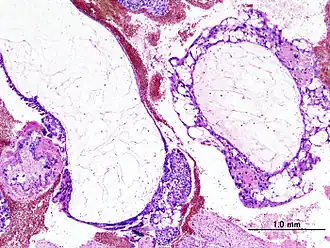

![]() Гистопатологическая картина пузырного заноса (полный тип). Окраска гематоксилином и эозином. | |

Пузы́рный зано́с — продукт зачатия, при котором не происходит нормального развития эмбриона, а ворсины хориона разрастаются в виде пузырей, наполненных жидкостью. Одно из проявлений трофобластической болезни, является её доброкачественным вариантом.

Пузырный занос бывает полным, при котором отсутствуют ткани эмбриона, и неполным, при котором эмбрион или его отдельные элементы присутствуют. Полный пузырный занос наблюдается вследствие оплодотворения дефектной яйцеклетки, не имеющей хромосом. В процессе дальнейшего деления отцовские хромосомы удваиваются, однако такая зигота является нежизнеспособной, так как эмбрион не образуется и происходит только рост ворсин. Неполный пузырный занос образуется в связи с оплодотворением яйцеклетки двумя сперматозоидами, поэтому клетки в этом случае содержат большое количество дополнительных хромосом, что также делает продукт зачатия нежизнеспособным. Ткань пузырного заноса вырабатывает большое количество хорионического гонадотропина, который приводит к образованию в яичниках лютеиновых кист. В 15-20 % случаев пузырный занос трансформируется в хорионэпителиому — злокачественная опухоль, то есть внедряется в здоровые ткани и даёт метастазы.